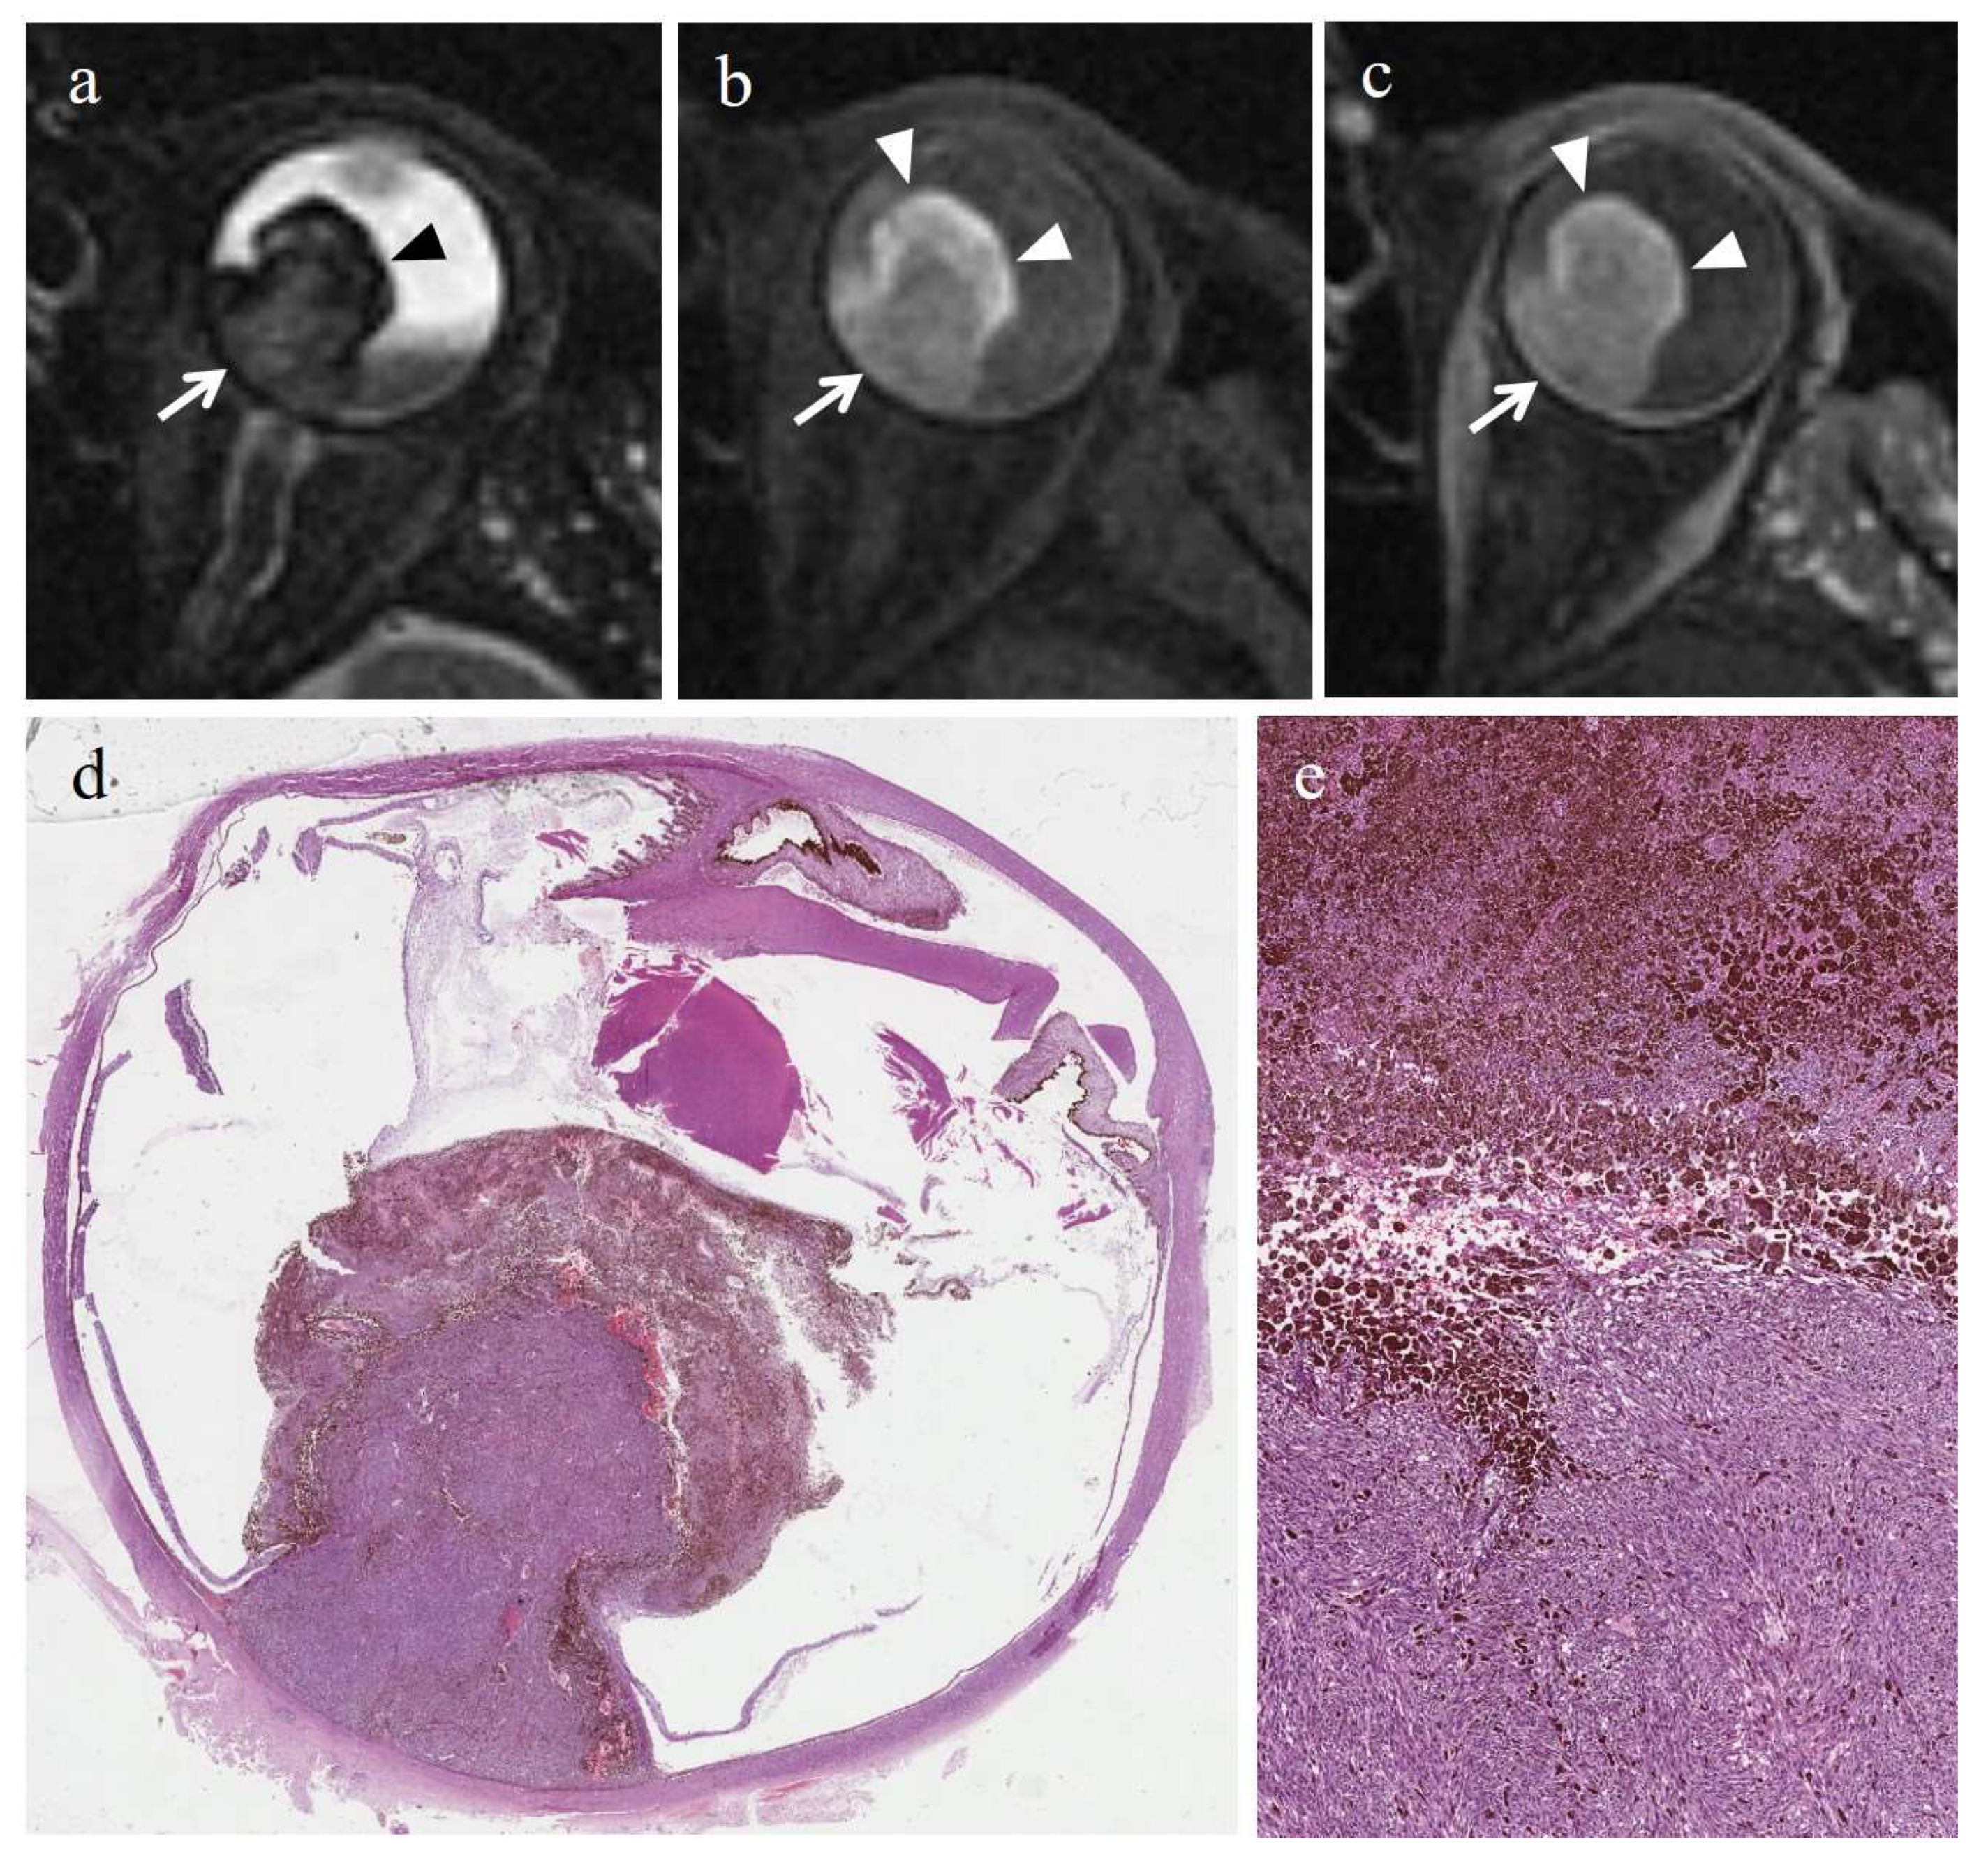

| MR Finding | T2 | T1 | Gd-T1 | DWI |

|---|---|---|---|---|

| Radiation-induced necrosis | ![]() Low signal | ![]() High signal | ![]() No enhancement | ![]() Low signal |

| Radiation-induced necrosis with viable tumor tissue | ![]() M RIN | ![]() M RIN | ![]() M RIN | ![]() M RIN |

| Hemorrhagic necrosis in untreated melanoma | ![]() High signal | ![]() Low signal | ![]() No enhancement | ![]() Low signal |

low signal;

high signal;

no enhancement; M: melanoma; RIN: radiation induced necrosis.| Patient | T2 | T1 | Gd-T1 | DWI | ADC × 10−3 mm2/s ** |